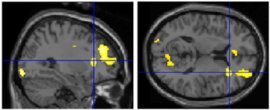

- method: observers naïve to art criticism placed in fMRI while viewing images of Classical and Renaissance sculptures

- stimuli: _________ (original) or modified images

- canonical images all had golden ratio among body parts

- viewing conditions:

observation (view images “as if they were in a museum”; non-evaluative)

aesthetic judgment

- analyses:

1) compared brain responses to canonical and modified sculptures

2) compared brain responses to beautiful and ugly sculptures (based on observer’s aesthetic judgment)

- findings: canonical images were strongly preferred over modified images

1) canonical sculptures activated right insula (mediates emotions; connects to/from amygdala): evidence for _________ beauty (“I can see why people like that.”)

right insula activity

2) beautiful images activated right amygdala (responds to learned emotional information): evidence for __________ beauty (“I like that.”)

right amygdala activity

- conclusion: both of these non-mutually exclusive processes contribute to appreciation of artwork